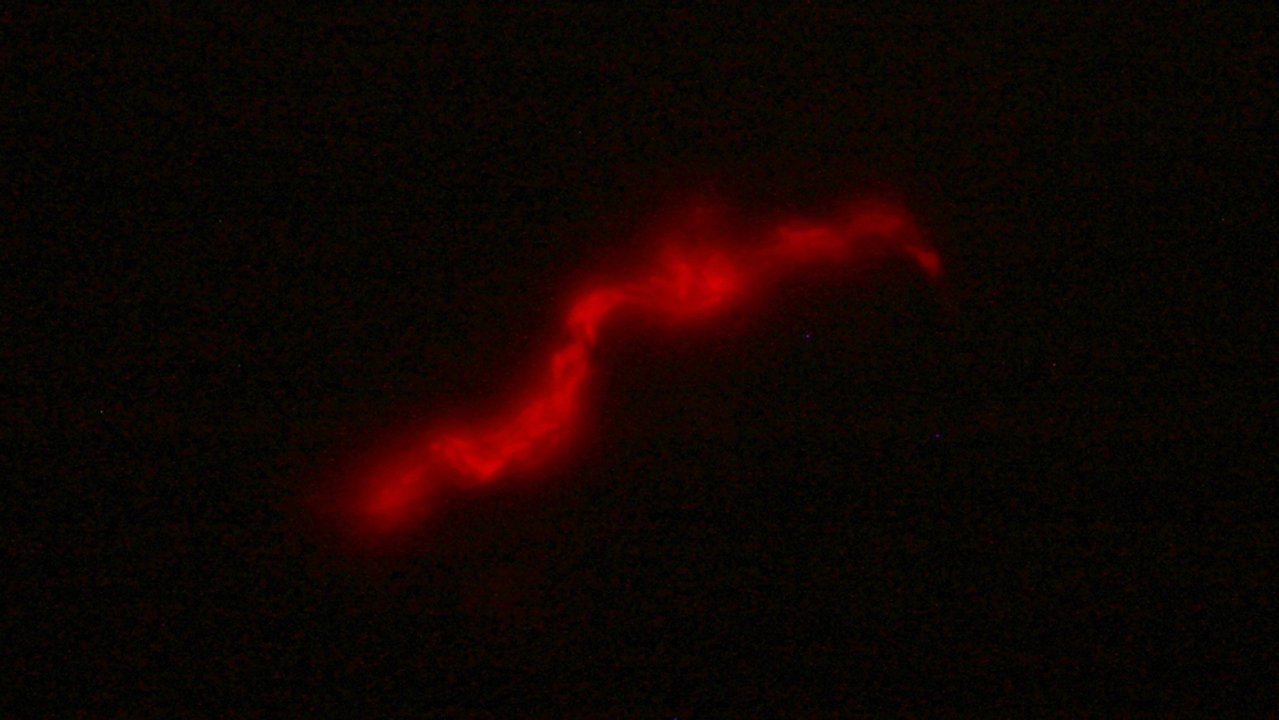

El kit está dotado de un bacteriófago, es decir de un tipo de virus que cuando entra en contacto con la bacteria de la tuberculosis, presente en la muestra de esputo del paciente, expresa una proteína fluorescente lo que permite una lectura directa mediante microscopía de fluorescencia. A futuro plantean automatizar la detección, empleando un microscopio de bajo costo y un programa que por IA pueda contabilizar bacterias fluorescentes en la muestra del paciente reduciendo los tiempos de lectura y la subjetividad del operador.